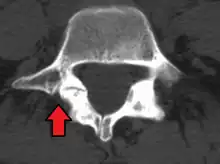

Isthmic anterolisthesis is where there is a defect in the pars interarticularis.[34] It is the most common form of spondylolisthesis; also called spondylolytic spondylolisthesis, it occurs with a reported prevalence of 5–7 percent in the US population. A slip or fracture of the intravertebral joint is usually acquired between the ages of 6 and 16 years, but remains unnoticed until adulthood. Roughly 90 percent of these isthmic slips are low-grade (less than 50 percent slip) and 10 percent are high-grade (greater than 50 percent slip).[31] It is divided into three subtypes:[35]

• A: pars fatigue fracture

• B: pars elongation due to multiple healed stress effects

• C: pars acute fracture